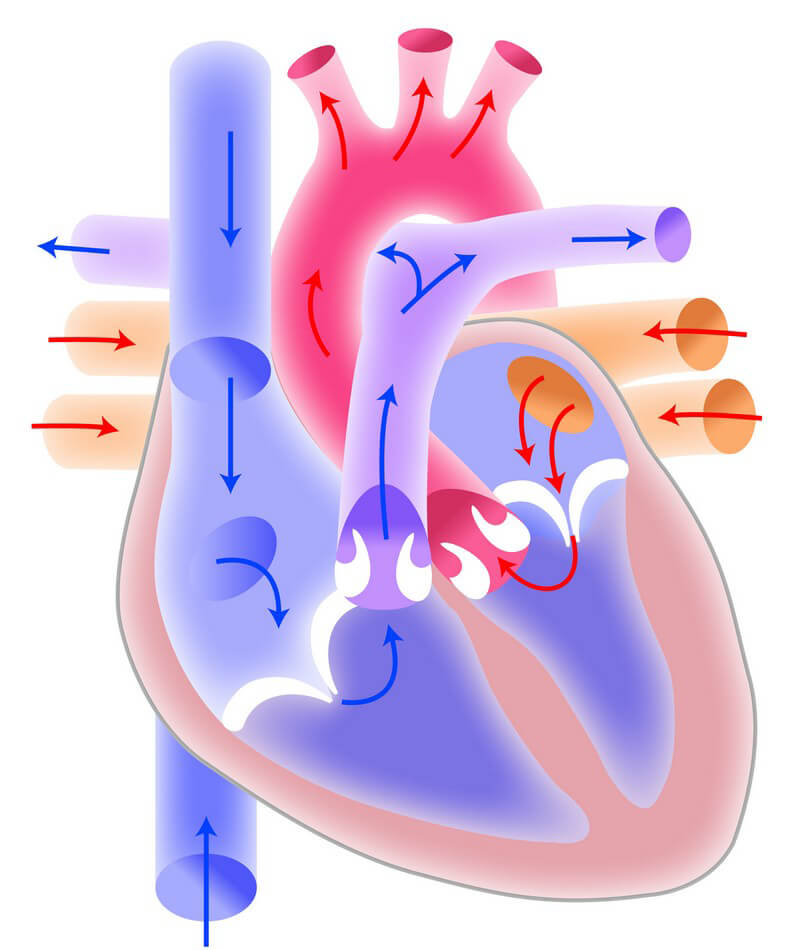

Die Pumpleistung ist die Menge des Blutes, die das Herz innerhalb einer bestimmten Zeit in den Blutkreislauf pumpt. Das gesunde Herz eines erwachsenen Menschen pumpt in Ruhe etwa 5 bis 6 Liter pro Minute. Bei einer körperlichen Belastung steigt dieses Herzminutenvolumen auf 20 bis 25 Liter. Krankheiten können die Pumpleistung des Herzens unnatürlich senken oder steigern.. In jeder Minute wird so einmal die gesamte Blutmenge – beim Erwachsenen fünf bis sechs Liter – durch den Körper befördert. Doch wie schafft das Herz jeden Tag diese Schwerstarbeit und wie funktioniert diese menschliche Pumpe? Herz-Kreislauf-System: So fließt das Blut. Das Herz ist das Zentrum des Blutkreislaufs.

Das Herzzeitvolumen (HZV, englisch cardiac output CO) ist das Volumen des Blutes, das pro Zeitspanne vom Herzen gepumpt wird (Volumenstrom).Die übliche Maßeinheit in der Humanmedizin ist Liter pro Minute, wobei dann vom Herzminutenvolumen (HMV), früher auch Minutenvolumen des Herzens, gesprochen wird.. Das Herzzeitvolumen ist ein Maß für die Pumpleistung des Herzens bezüglich der.. Der venöse Rückstrom zum Herzen bestimmt ganz wesentlich, wie viel Blut das Herz jede Minute auswirft. Abhängig von diesem Rückfluss pumpt das Herz automatisch das zurückströmende Blut in den Körperkreislauf. Je mehr Blut zurückströmt, desto mehr Blut wird vom Herzen ausgeworfen und umgekehrt.